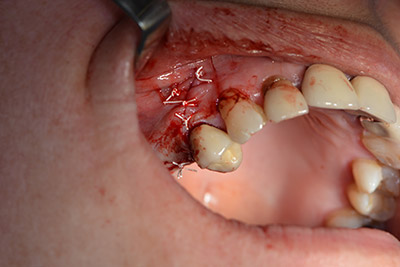

Eine resorbierbare Membran bildet die Barriere nach bukkal und deckt das Augmentat ab. Zum Schluss wird speicheldicht vernäht. (Abb. 15 bis 19).